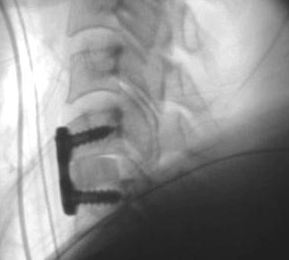

Surgical treatment typically involves taking the pressure off the nerves or spinal cord at one or more levels and fusion of the involved segment(s) with a bone graft and instrumentation (plates, rods and screws) (see below). The surgery may be performed from the front or back of the neck. Advanced imaging technology and electrical monitoring of the nervous system helps to improve patient safety and outcomes. Most patients need a brief period of close neurological monitoring after surgery followed by progressive return to their usual activities. Severely affected patients with myelopathy may require inpatient rehabilitation; other patients may be discharged within a day after surgery. A rigid neck collar may need to be worn for up to three months. The length of time off work is highly variable depending on the nature of the job, the type of surgery performed and the patient's response.

X-ray of the neck showing plate and screws in place after removal of the disc